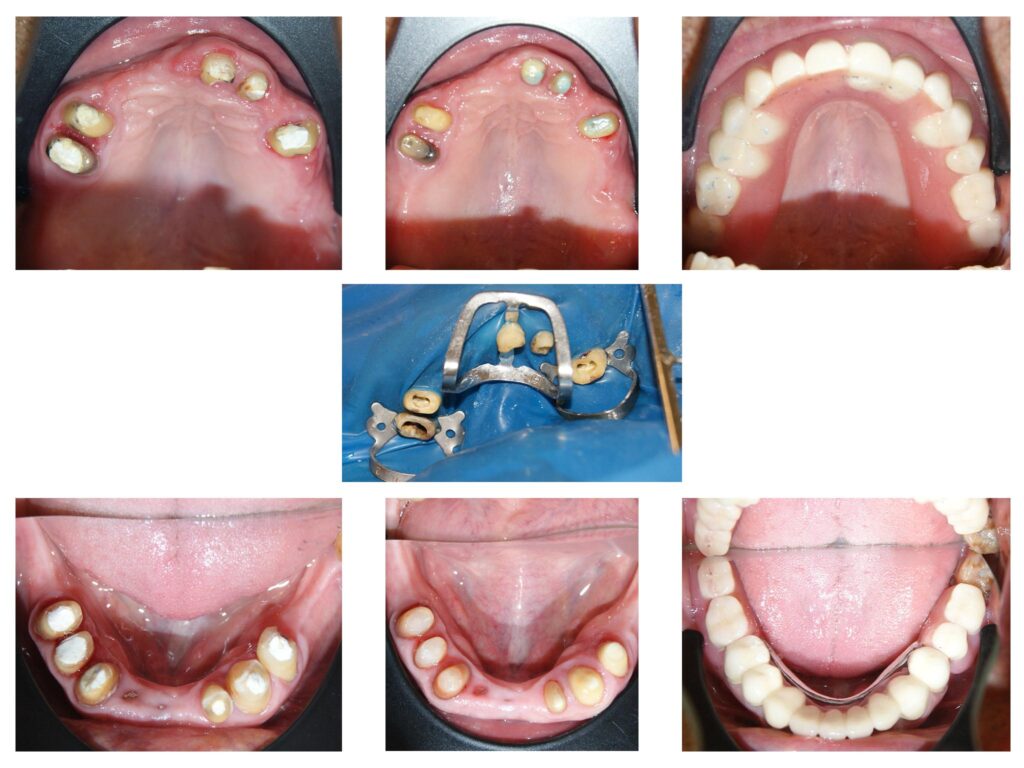

Un caz de o dificultate estestică majoră pe care l-am rezolvat cu succes împreună cu tehnicienii noștri. Am reușit să salvăm toți dinții deși erau destul de mult afectați și ulterior să îi îmbracăm cu coroane solo. Cromatica coronițelor este atât de potrivită încât în final nu se diferențiază de dinții naturali printre care sunt intercalate